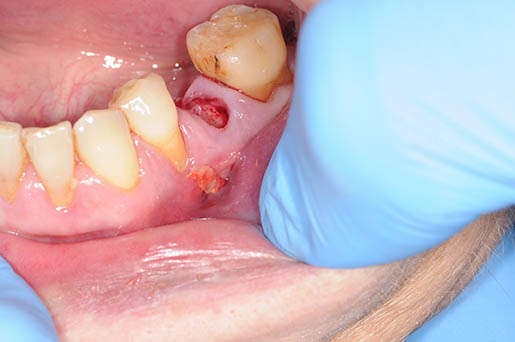

caso di osteonecrosi mandibolare inferiore di destra

Chirurgia

L’approccio chirurgico prevede l’asportazione dell’osso necrotico ed è generalmente consigliato per gli stadi più avanzati e o terminali della MRONJ.

L’intervento chirurgico rappresenta il rischio di recidiva con estensione delle aree di esposizione ossea e aggravamento dei sintomi. Diverse alternative e terapie aggiuntive (laser a basso livello, ossigeno iperbarico, ozono terapia) e diversi agenti biologici (contribuzione piastrinica autologa, concentrati, fattori di crescita e differenziazione ricombinanti, ormone paratiroideo) sono stati proposti in letteratura con risultati positivi.

Programmare un’ intervento chirurgico dovrebbe quindi rappresentare l’ estrema ratio per la risoluzione di questa problematica.